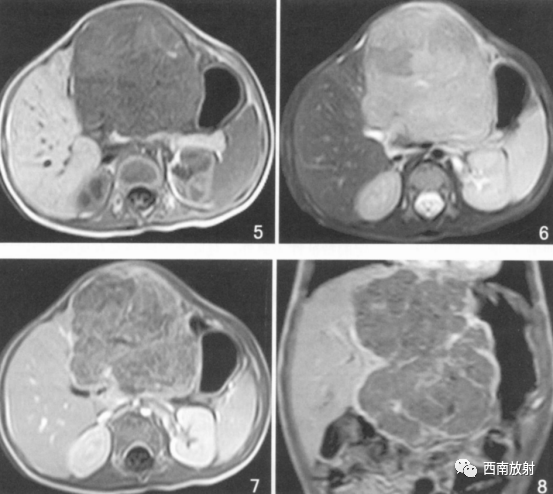

▲病例3:肝母细胞瘤。图5T1WI肝左叶巨大低信号肿块,中间见点状高信号影,考虑出血。图6为T2WI肿块呈明显高信号用哪个,增强扫描病灶内部不均匀强化,假包膜线状强化,坏死区无强化。